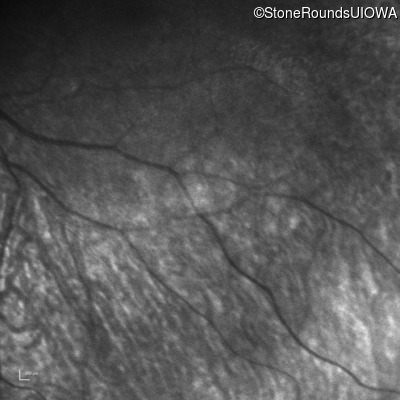

Infrared Fundus Photograph - Left -

No Light Perception

Exemplar

Expanded OCT Stack

×